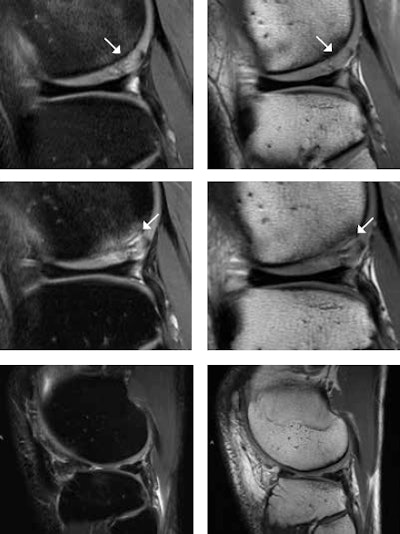

A 25-year-old male tennis player after microfracturing (MFX), or bone drilling. With MFX, small holes 3- to 4-mm apart from each other are drilled into the subchondral bone to stimulate the bone marrow (stem cells). MR images one year after MFX (top row) show persistent mild subchondral bone marrow edema and high T2 signal change of the cartilage (white arrows) at the posterior portion of the lateral femoral condyle. At two-year follow-up (middle row), there is progressive subchondral bone marrow edema, undermining fluid at the interface between the subchondral bone and the cartilage, and interstitial tears of the detached cartilage (white arrows). This is consistent with incomplete integration of the chondral defect. MR images four years after MFX (bottom row) surprisingly show complete integration of the chondral defect without any additional treatment. Images courtesy of Dr. Claudia Weidekamm.Ultrasound still plays an important role in sports injuries, as an immediately available on-the-field imaging modality at sports events and also as a complementary modality for assessing muscle and tendon injuries or post-traumatic effusion/synovitis. "Nowadays, we face the problem that ultrasound is performed more and more by sonographers. The consequence is that radiologists are losing their skills for performing the ultrasound examination," she noted.